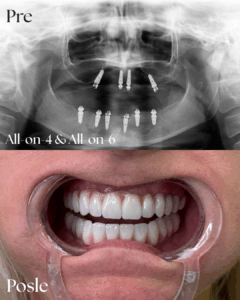

ALLON4-ALLON6

In Dental – Galleria

Rad1